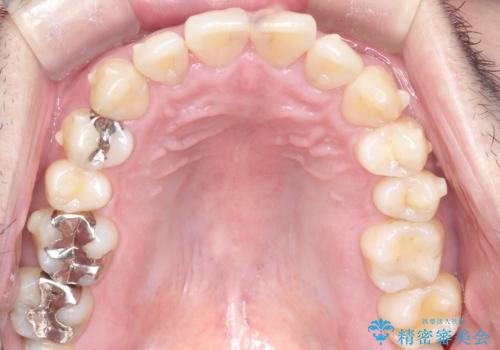

全体的ながたつきをインビザラインで改善

- 全体的ながたつきを主訴に来院されました。

歯と歯の間をわずかに削って、スペースをつくり並べる計画としました。

しっかりと、マウスピースの装着時間を守っていただいたので、スムーズに治療をおえることができました。